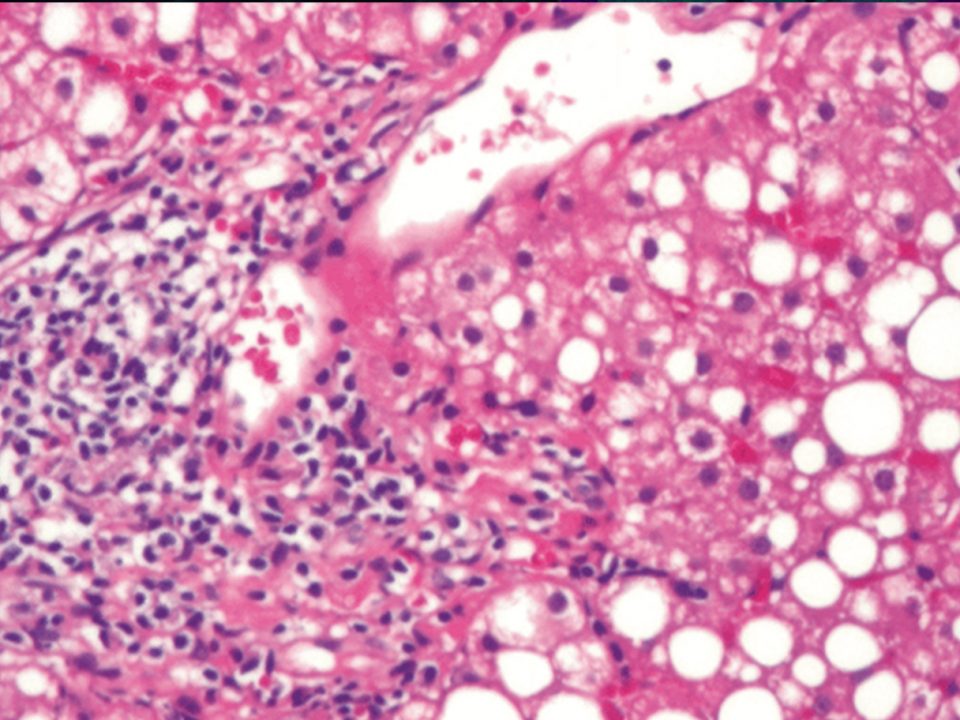

D-galactosamine is known to cause acute liver damage in animal models. The mechanism of D-galactosamine hepatotoxicity is not fully understood but D-galactosamine is believed to cause an intracellular deficiency of uridine metabolites leading to acute liver failure10. As illustrated in Figure 1, acute liver injury by D-galactosamine is associated with waste accumulation, systemic inflammation and impaired regeneration. These three problems are also seen in humans and often contribute to death after drug induced acute liver injury which makes the porcine model of D-galactosamine acute liver failure an appropriate large animal model for testing extracorporeal liver assist devices.